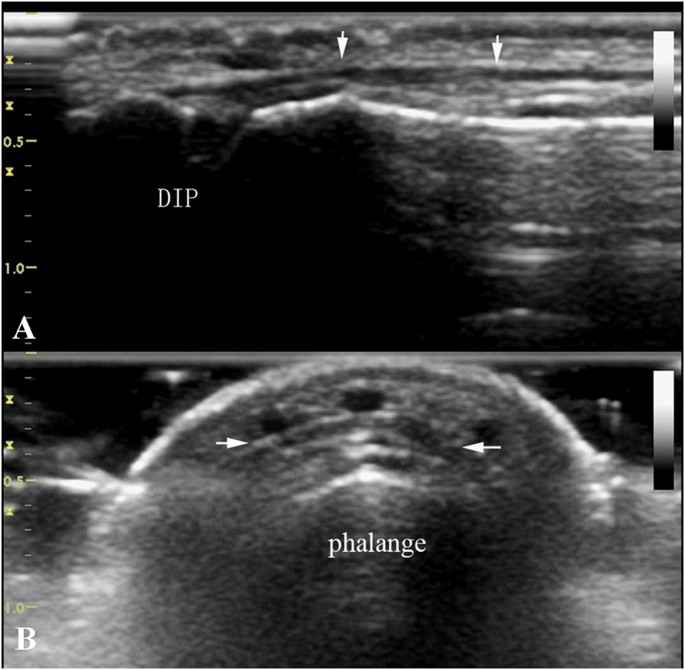

Normal finger extensor tendons appeared as slightly hyperechoic thin fiber bundles in longitudinal and transverse planes on ultrasonography9, 10. As shown in Fig. 1, the end of extensor tendon is attached to the base of the distal phalanx, and their integrity could be evaluated by sliding dynamic examination.